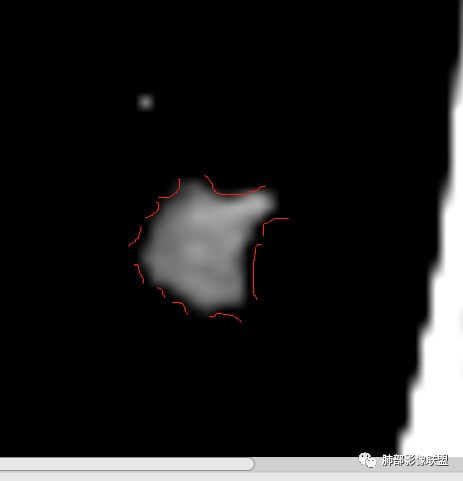

左肺上叶后段病灶,有毛刺,有胸膜牵拉,有血管滋养,好像还可以看见内部空泡,深分叶,边界比较清楚,考虑恶性肿瘤。

左肺上叶实性不规则结节,有深分叶,短毛刺,有切迹,有血管集束,有胸膜牵拉,常规考虑恶性,鉴别炎性结节

女性,左上肺实性结节,有毛刺,有血管进入,边缘彭隆,月牙铲,深分叶,边界比较清楚,胸膜牵拉,考虑腺癌。

中年女性,实性不规则结节,分叶,毛刺,有切迹,血管集束,胸膜牵拉,强化,常规考虑恶性腺癌,鉴别,隐球菌(夹馍抗原),结核(强化少)

1.胸膜下略不规则实性密度结节影,孤立,缺乏典型深分叶,可见淡薄边界模糊磨玻璃晕,可见相对细长软毛刺。

2.如南边老师分析,病灶缺乏边缘膨隆优势,甚至部分平直内收。

3.病灶收缩力不强,整体强化程度不显著。

4.综上,病灶更符合炎性,如隐球菌感染等,而不大符合肺腺癌。具体到机化性肺炎略有些出乎预料。